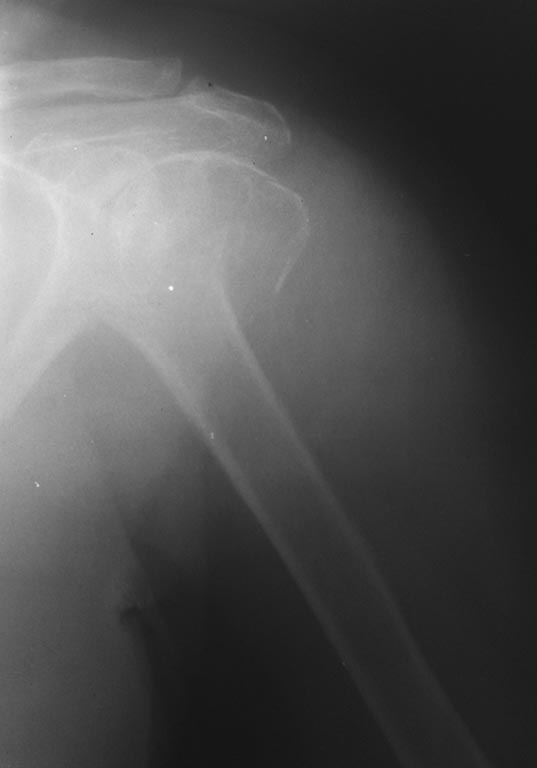

Добрый день, коллеги! Трёхфрагментарный перелом проксимального отдела плечевой кости.

(большой бугорок без смещения). Больная 1939 г.р. сопутствующая патология: ИБС. ПИКС. Ревматоидный полиартрит.

Плюс к данному перелому- перелом шейки бедра(планируется эндопротезирование).

Какой вид остеосинтеза предпочтительнее? Фиксация винтом большого бугорка винтом через прокол и напряжённые гамма-спицы, или всё таки пластина? Заранее спасибо!